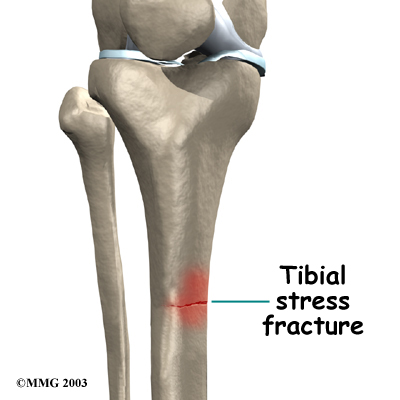

A stress fracture in the tibia is a serious problem that at first may have the same symptoms as shin splints. A stress fracture is a crack in a weakened area of bone. Continual stresses from running on hard surfaces or from heavy strain in the tibialis muscles can weaken and eventually fracture the tibia. People with shin pain who try to work through it sometimes end up developing a stress fracture in the tibia.

Physician Review

Your doctor may order X-rays to make sure you don't have a stress fracture. However, recent stress injuries may not show up on X-ray for the first few weeks. In these cases, a bone scan may be ordered. A bone scan involves injecting tracers into your blood stream. The tracers then show up on special X-rays of your leg. The tracers build up in areas of extra stress to bone tissue. The extra stress can be caused by a stress fracture or an inflamed periosteum (bony covering). This condition is called periostitis.